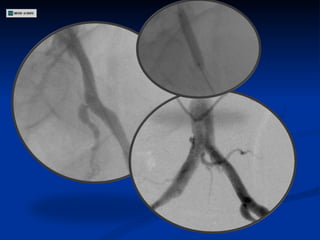

ECODOPPLER DE VASOS DEL CUELLO Estenosis 80-90 % en segmento inicial de Carótida Interna Derecha Estenosis 50-60 % en Carótida Interna Izquierda Carótidas externas permeables con flujos conservados Arterias Vertebrales permeables

Angiografía

CONDUCTA

ECODOPPLER DE VASOSDEL CUELLO Estenosis 80-90 % en segmento inicial de Carótida Interna Derecha Estenosis 50-60 % en Carótida Interna Izquierda Carótidas externas permeables con flujos conservados Arterias Vertebrales permeables